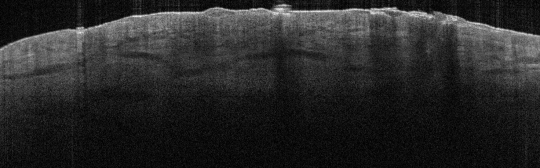

VA35: Left Temple, Actinic Keratosis, Hypertrophic

- White arrows indicate return to dermal collagen texture and reflectivity

VA35: Left Temple, Adjacent, Normal